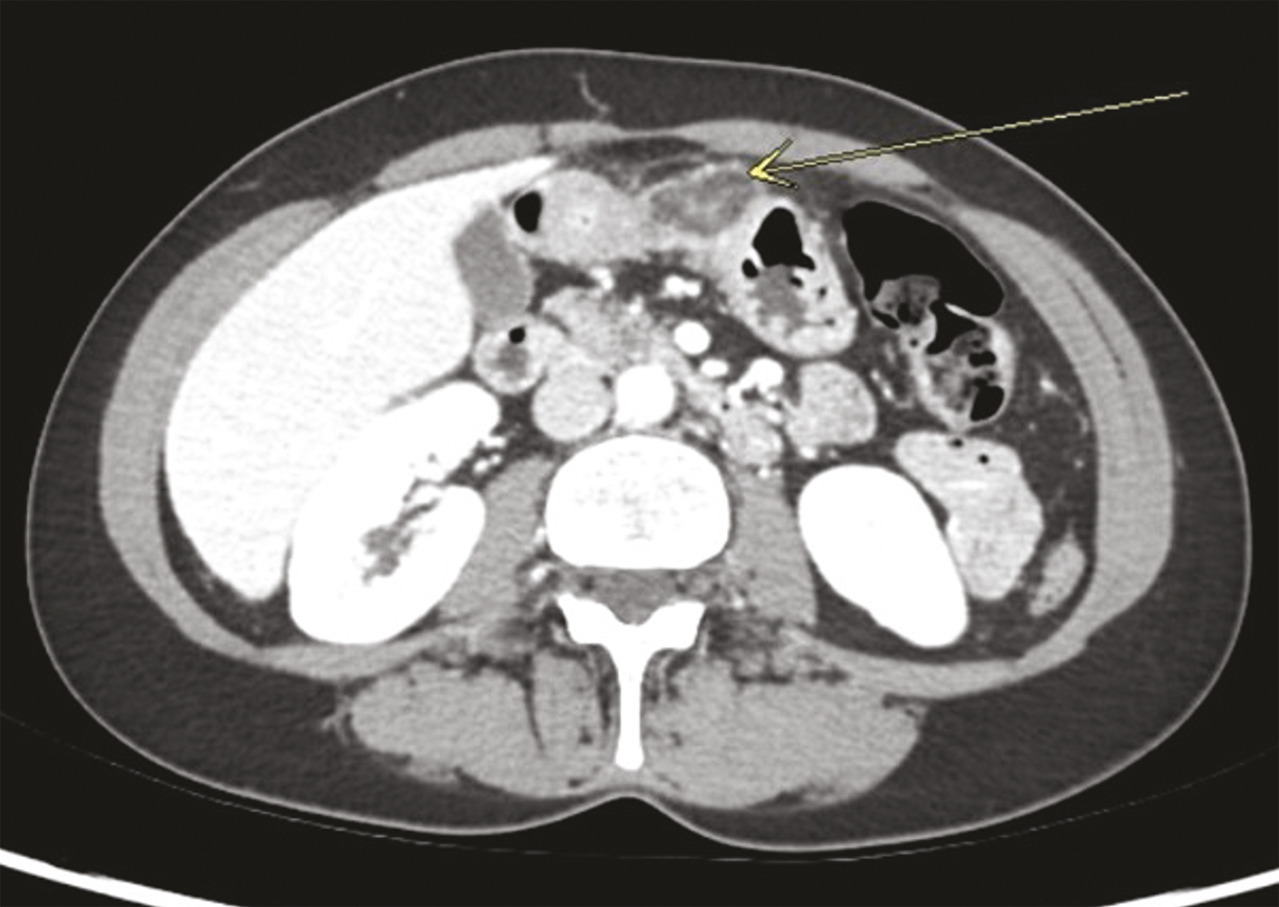

Biologiquement, la protéine C réactive (CRP) était à 31 mg/L, le bilan hépatique était normal. L’échographie a mis en évidence une vésicule alithiasique à parois fines sans dilatation des voies biliaires. La tomodensitométrie avec injection de produit de contraste, réalisée en urgence, a révélé un aspect typique de torsion de frange épiploïque (ou appendagite épiploïque) du côlon transverse, latéralisée à droite (figure).

Une frange épiploïque est un appendice graisseux suspendu au côlon, du cæcum au sigmoïde, de taille moyenne de 3 à 5 cm. Elle est recouverte de péritoine et possède une vascularisation terminale avec une artère et une veine. Lors d’une torsion, on observe une thrombose de cette veine, suivie d’une inflammation. Elle survient principalement chez les adultes entre 20 et 50 ans. Son incidence n’est pas réellement connue mais elle représente environ 5 % des tableaux abdominaux aigus. Cliniquement, le signe le plus fréquent est une douleur aiguë, le plus souvent en fosse iliaque droite, parfois récurrente. Les signes tels que la diarrhée ou les vomissements ne sont pas fréquents. Une fébricule est possible. Les examens biologiques sont peu contributifs, hormis un ­syndrome inflammatoire modéré. L’examen clé est le scanner abdo­minal injecté. Il montre une image typique, ovalaire, dépendante du côlon, dont la densité est graisseuse, avec un liseré prenant le contraste en périphérie (figure).